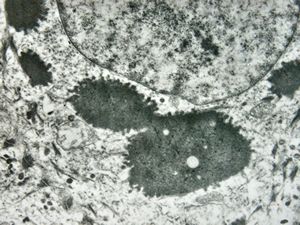

F, 7y. | molluscum contagiosum … virions

F, 7y. | molluscum contagiosum … virions